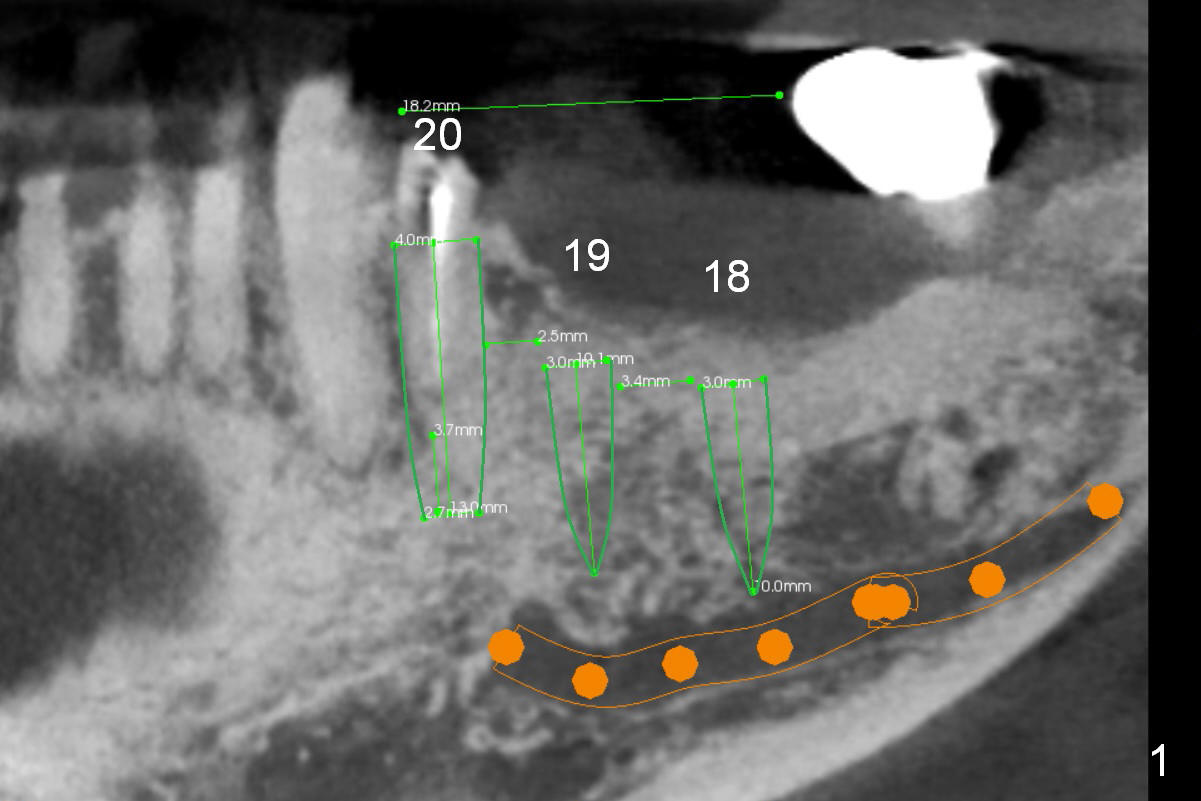

A 71-year-old man requests restoration at #18-20 (Fig.1). Placing implants at the narrow ridge of the sites of #18 and 19 is quite challenging (Fig.3,4), as compared that at #31 (Fig.5). Since the bone density at the crest is high (1200-1500 u), use a surgical high speed fissure bur for sectioning the crest, followed by BEB at 11 mm. It appears safer to place 1-piece implant (Fig.3) than 2-piece one (Fig.4). Since the total mesiodistal distance for #18-20 is 18 mm, splinting the three-units should be a sound treatment option.

After removing the residual root at #20, no antibiotic will be used for socket disinfection except gauze. It seems that an implant smaller than 4 mm is needed (Fig.1,2).